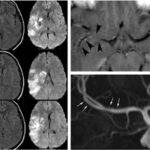

Asimismo, una investigación encontró patrones comunes de lesiones cerebrales a través de la neuroimagen mediante una recopilación extensa de estudios radiológicos vinculados con casos de adolescentes con problemas de adicción a sustancias psicoactivas ilegales, desde 2006 hasta 2016. El estudio constató dos patrones coincidentes. El primero fue la lesión cerebral difusa simétrica de la sustancia blanca subcortical con afectación cerebelosa preferencial, o leucoencefalopatía. El segundo lo constituyen múltiples focos de infartos isquémicos en una distribución territorial no arterial patrón isquémico.(21)

En esta investigación que se viene señalando, se puede mencionar el caso de un joven de 16 años, con alteración aguda del estado mental por inhalación de vapor de heroína. Se le efectuó una RM que evidenció hiperintensidades en T2 de la sustancia blanca simétrica difusa infratentorial y supratentorial. El diagnóstico clínico en este caso fue rabdomiólisis, que afecta predominantemente la musculatura posterior del cuello(21) (ver Imágenes 11 y 12).

Otro caso que merece ser comentado es el de un adolescente de 15 años que presentó encefalopatía y signos extrapiramidales por ingestión de metadona. La RM evidenció focos de infartos agudos en el caudado y putamen, así como infartos corticales de la línea divisoria de aguas parietales(21) (ver Imagen 13).